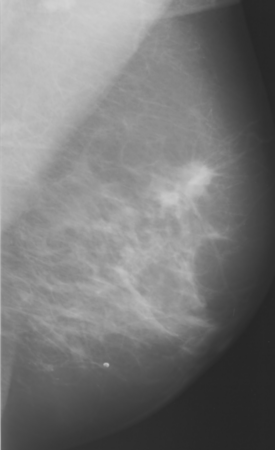

A typical example of image registration applied to mammographic

images is shown below.

| Reference Image |

Image to be Warped |

Difference After Registration |